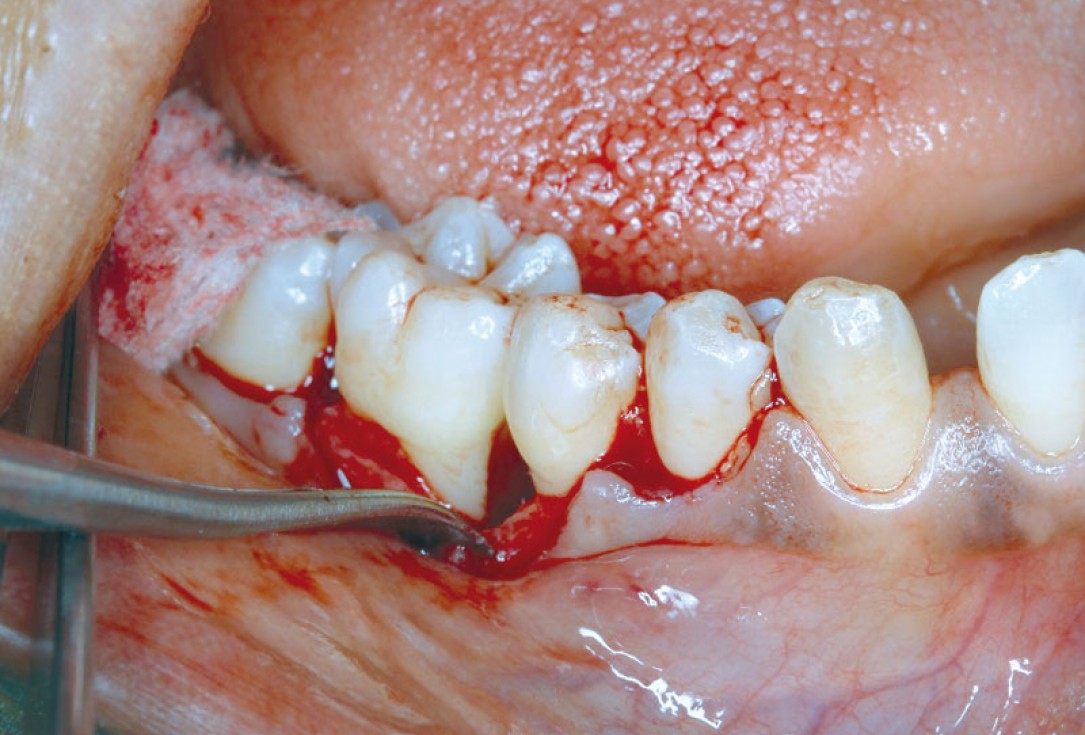

02/08 - Raised flap showing the defectRegeneration at LR6 with cerabone® and collprotect® membrane using simple papilla preservation technique - Dr. D. Chatzopoulou